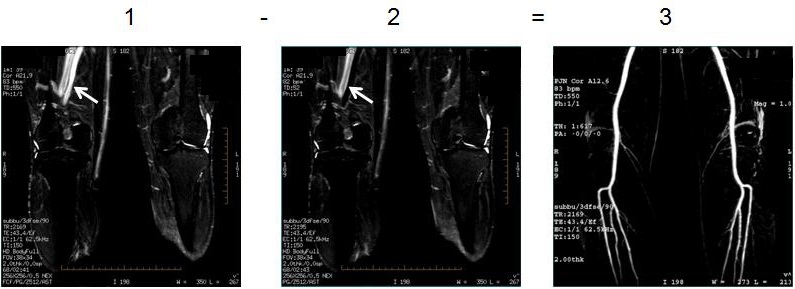

Inhance Deltaflow is a non-contrast agent MRA method. It acquires two 3D slabs: one during systolic phase and one during diastolic phase. A multi-phase SSFSE scan is acquired to determine the diastolic trigger delay for the Inhance Deltaflow acquisition.

The signal produced from arterial flow is sensitive to the cardiac cycle. During systolic phase, arterial flow is fast resulting in a dark signal. During diastolic phase, arterial flow is significantly slower resulting in a bright signal. Unlike arterial flow, venous and background signal are relatively insensitive to the cardiac cycle. Subtraction of the systolic slab from the diastolic slab results in the visualization of the arteries with good background suppression. A STIR pulse can be applied to both the systolic and diastolic acquisition for additional fat suppression.

| Number | Description |

|---|---|

| 1 | Systolic |

| 2 | Diastolic |

| 3 | Subtracted image with artery visualization |